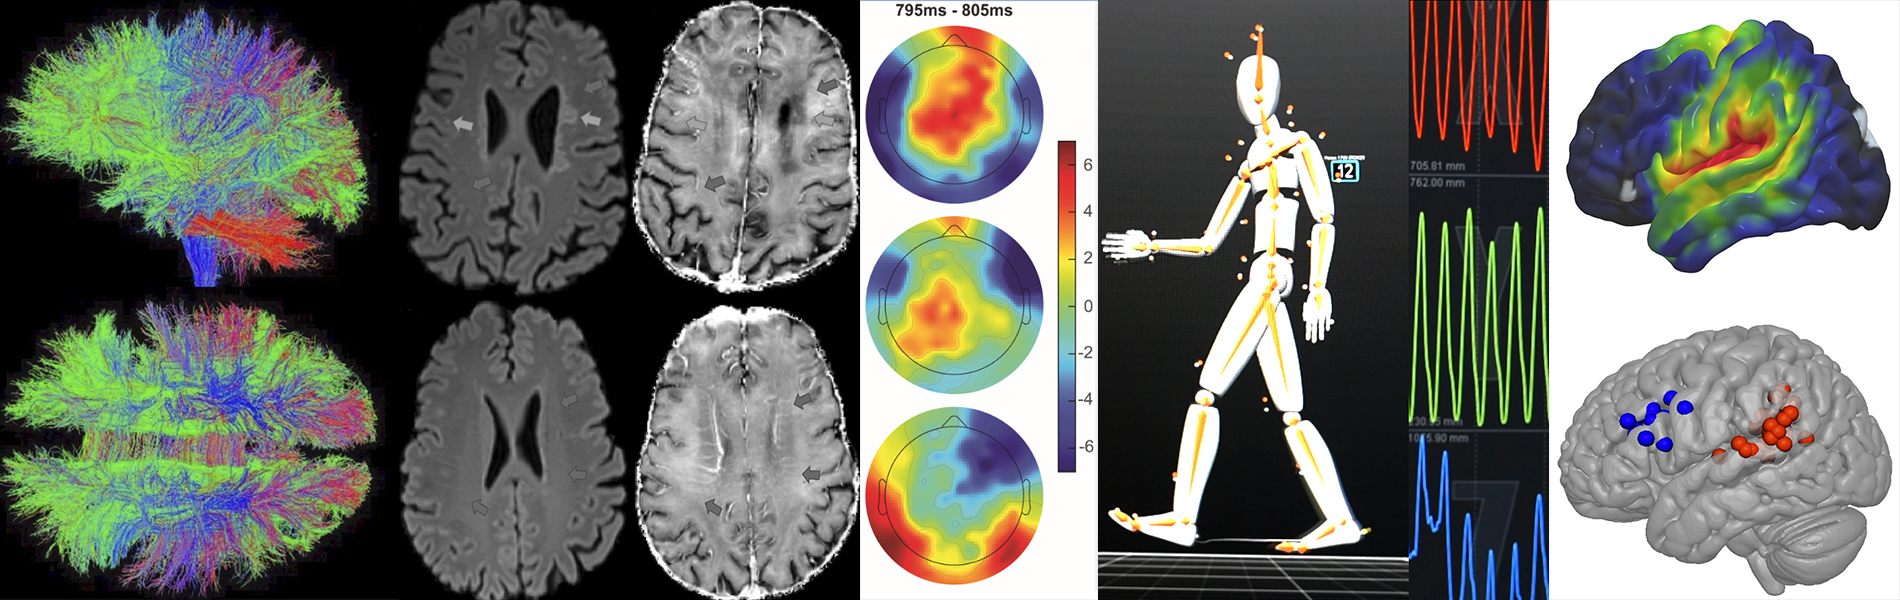

The University of Rochester Center for Advanced Brain Imaging & Neurophysiology (UR CABIN) is a multimodal imaging facility that supports human and preclinical imaging research. Providing researchers with different methods of study CABIN supports a wide range of scientific discoveries – from basic to clinical neuroscience.

Our state-of-the-art brain imaging technologies:

- 3T Siemens Prisma MRI scanner

- 9.4T Bruker animal MRI scanner with PET insert

- High-density Electroencephalography (EEG)

- Eye tracking

- Mobile Brain Body Imaging (MOBI)